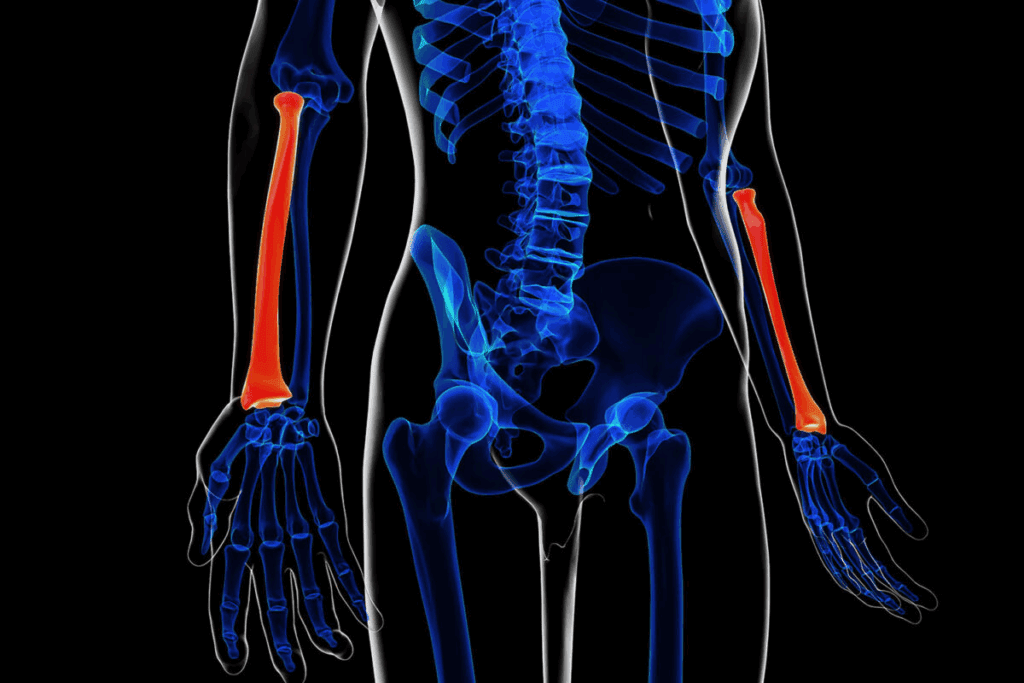

It’s important to know about L1 compression fractures to manage and treat them well. An L1 compression fracture happens when the L1 vertebra in the lumbar spine collapses or gets compressed.

A compression fracture is when a vertebra collapses, often because of osteoporosis or trauma. The L1 vertebra is key in the lumbar spine, supporting our body’s structure.

This collapse can cause chronic pain and deformity. Knowing about this injury is key to giving the right care.